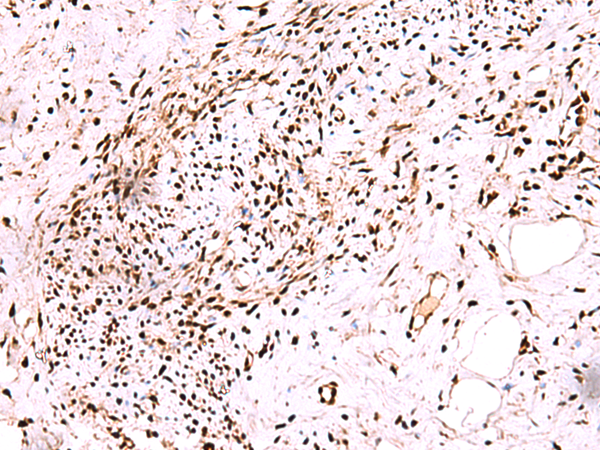

ELISA, IHC |

IHC positive control: |

Human cervical cancer and Human ovarian cancer |

IHC Recommend dilution: |

50-300 |